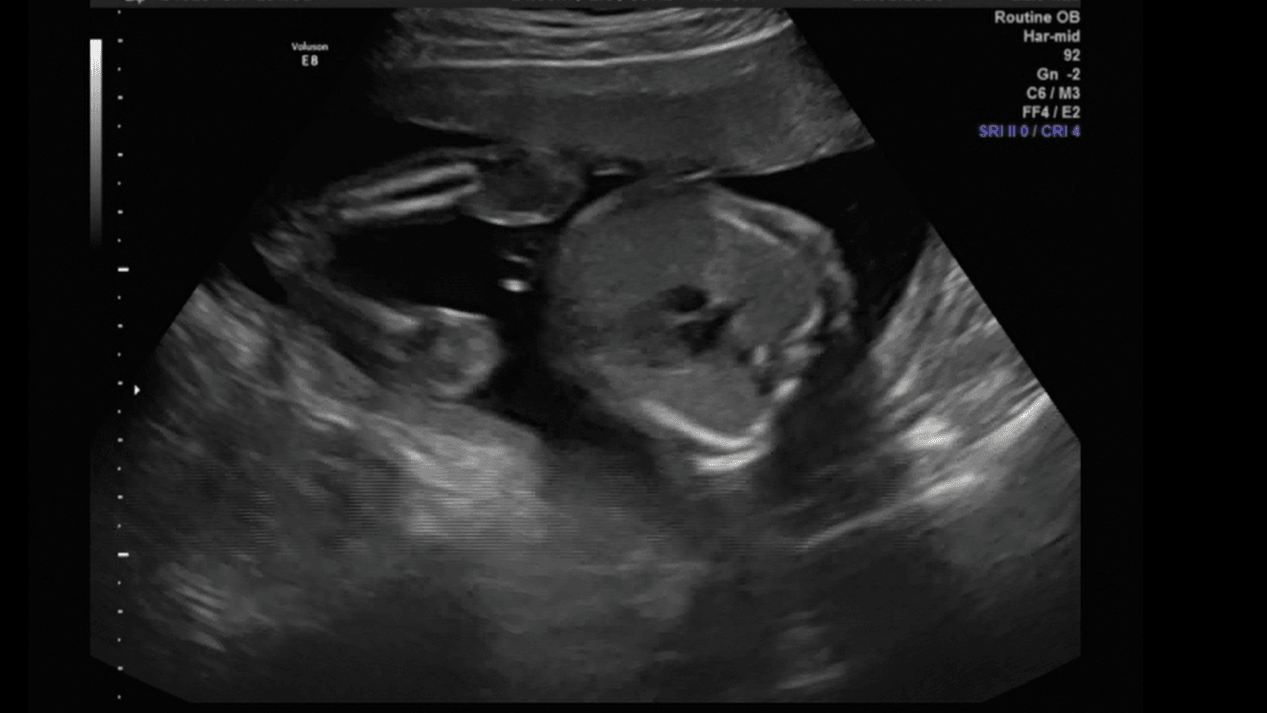

Ziewam sobie :)

19.png